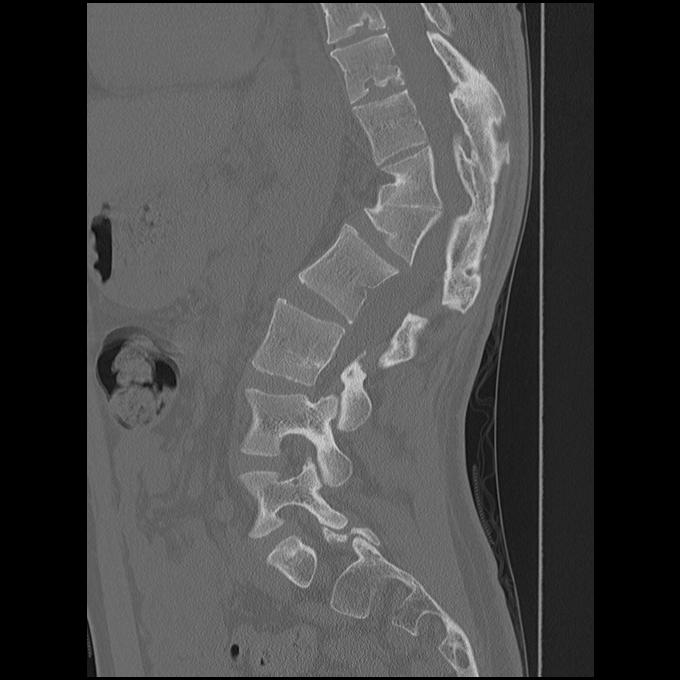

Type I - Failure of formation

Failure formation anteriorly + preservation of posterior elements

- hemivertebrae / wedge vertebrae

- most common

- produces the worst deformity

- NHx is one of relentless progression

- 7o per year

- most likely to result in paraplegia